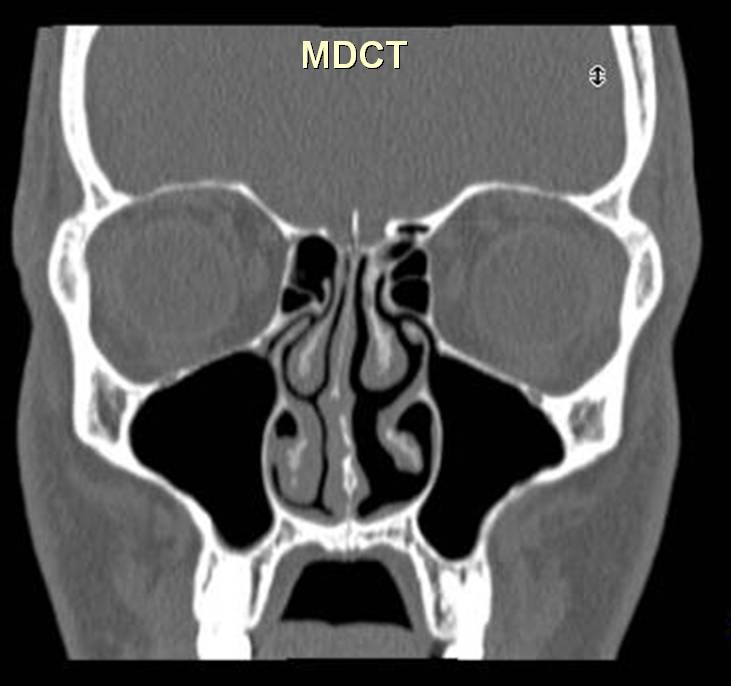

3. image: Paranasal sinus examination, coronal reconstructions (right panel: cone-beam CT; left panel: MDCT). Concha bullosa(asterisk) with ethmoidal infundibulum narrowing (arrow). Cone-beam CT and MDCT information correlates almost 100 %.